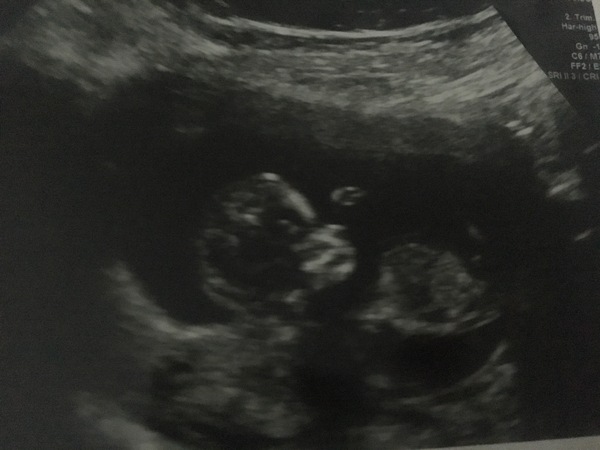

This shows the screening dates

September 2019 Babies #2

@knobjockey I have my first 12 week scan next week. Eeeek. Seeing the scan pics in here makes it all so real! There is actually a Baby in there lol. X

All good! She said if i do have a bicornuate uterus then it's very difficult to see and no detriment to baby who is growing as should be and definitely not septate. So that's a relief! Baby jumped a couple of times then became quite still. Sonographer was tapping my tummy To get baby to move but it wasn't playing ball. Anyway was great to see and it's exciting to see a real baby shape forming now. She dated me 11+6 so due 28th aug!

@Whisky2014 great news! The difference between wee blobs early on and then proper baby shape at 12 weeks is such a big one!

Lovely picture @Whisky2014, you must be so pleased 😊

So I went all the way back (2hr round trip) to have the blood redrawn which was annoying but they did a free scan whilst we were there to apologise. Can’t believe how much baby has grown in just a week. No wonder my poor muscles ache!

Also sonographer said baby looks fine and he’s be surprised if there was a problem which is positive :)